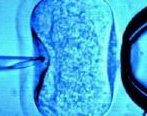

雌二醇水平达到多少才能做试管囊胚移植如何提高雌二醇水平

雌二醇水平达到多少才能做试管囊胚移植?如何提高雌二醇水平?